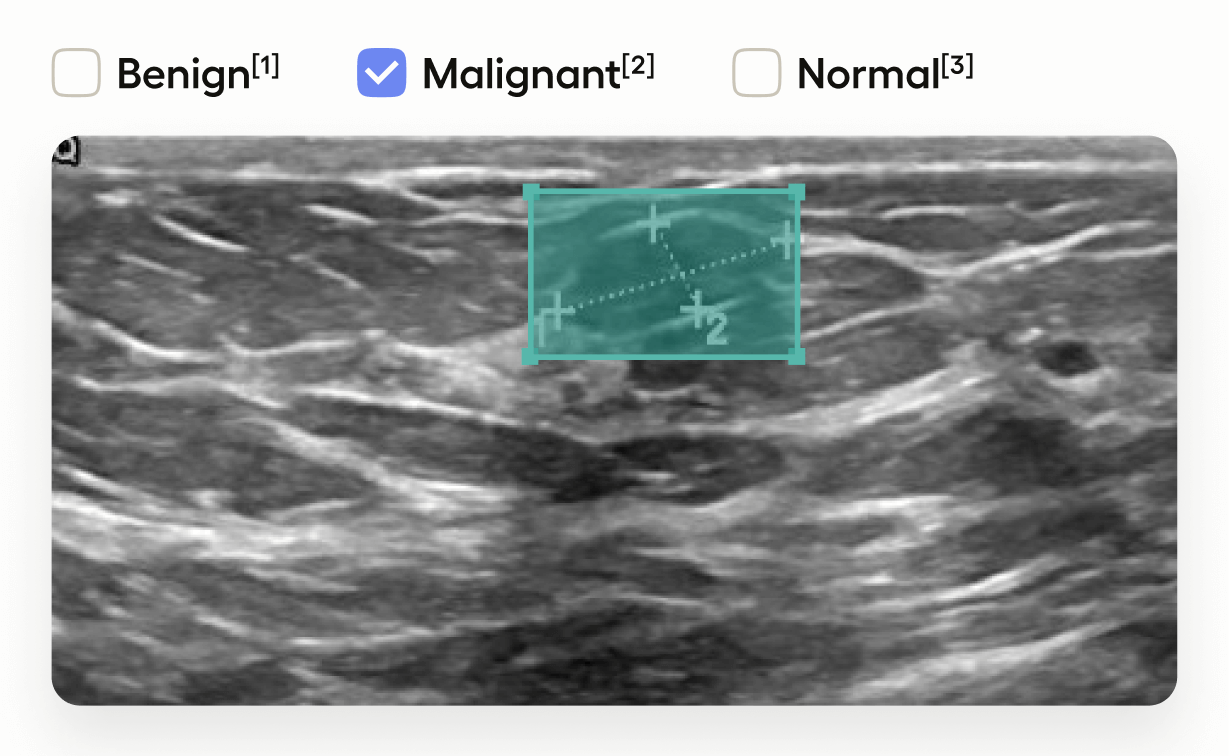

This template interface allows annotators to:

• Draw bounding boxes around areas identified as tumors in the image using the “Tumor” label.

• Classify the entire image by selecting one of “Benign”, “Malignant”, or “Normal”.

This setup is useful in medical imaging tasks where you need to localize tumors and also provide an overall assessment of the image.